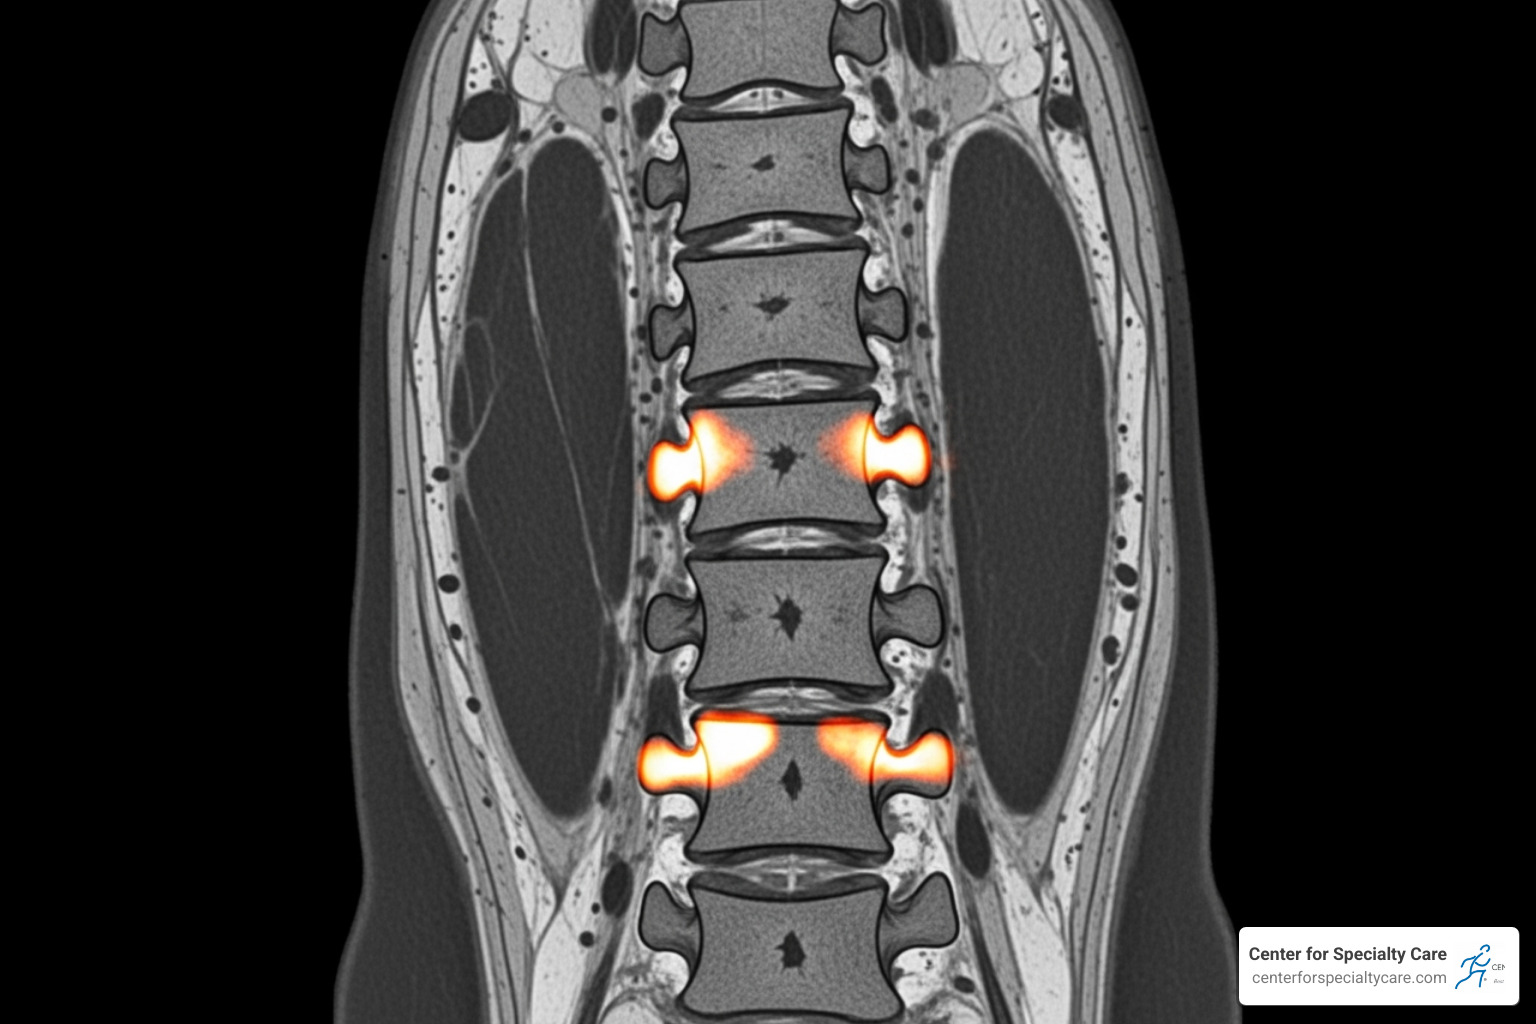

- Specific MRI Findings: Your MRI must show Modic Type I or Type II changes at the vertebral endplates (between L3 and S1). These changes are a key indicator of vertebrogenic pain.

- Complete Medical Records: This includes consultation notes, physical exam findings, and your MRI reports and images that clearly show Modic changes.

- An MRI clearly showing Modic Type I or Type II changes.